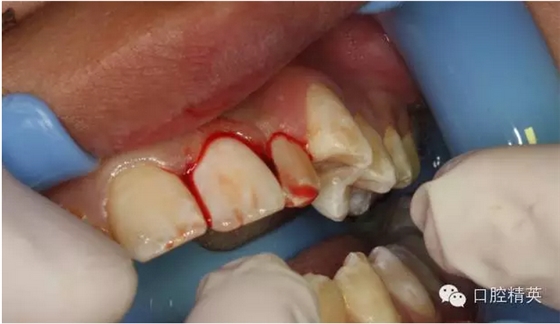

圖14.再植21離體牙